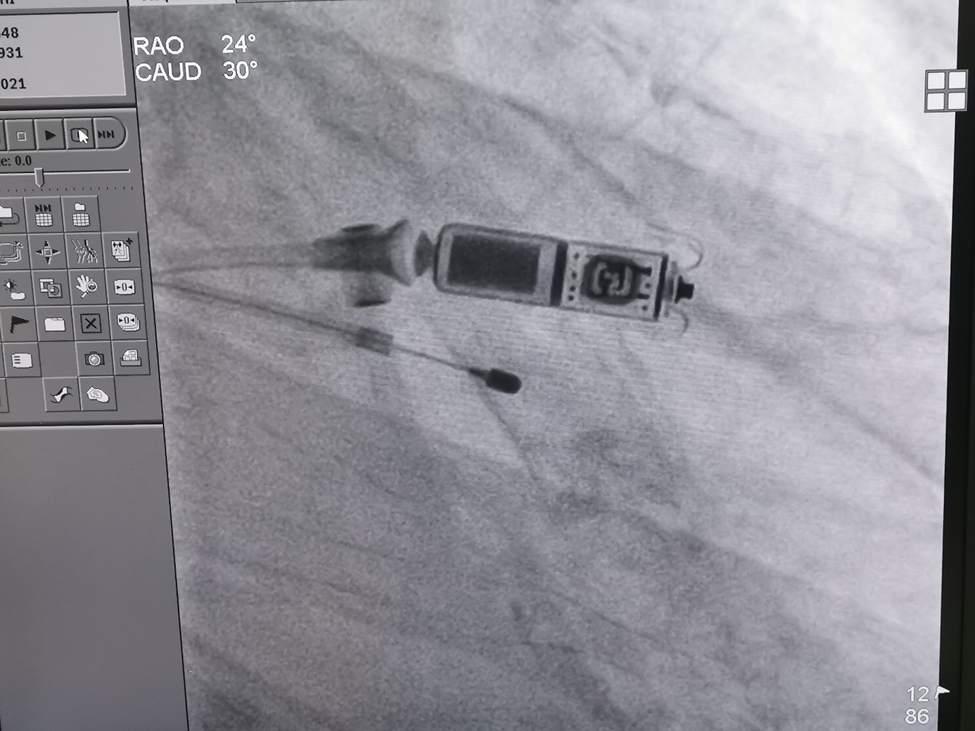

经过充分的术前准备,Micra无导线起搏器植入手术在局部麻醉下进行,通过股静脉穿刺,将起搏器通过导管植入到心腔内部,手术过程仅用半小时,术后体外程控测定各项参数良好。该起搏器无需植入心内膜导线,也无需在胸前皮下制作囊袋,减少了创伤与感染风险。而且Micra无导线起搏器直接植入在心腔内,无伤疤、无切口,患者术后几乎感觉不到起搏器的存在,无需制动,不影响患者日常生活,大大改善了患者的生存质量。